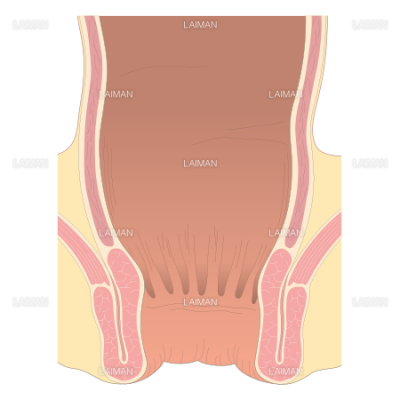

直腸断面 mサイズ Laiman Stockweb メディカルイラスト素材のダウンロード販売

下部直腸の構成図 mサイズ Laiman Stockweb メディカルイラスト素材のダウンロード販売

排便障害 よくわかる大腸肛門科

直腸脱 よくわかる大腸肛門科